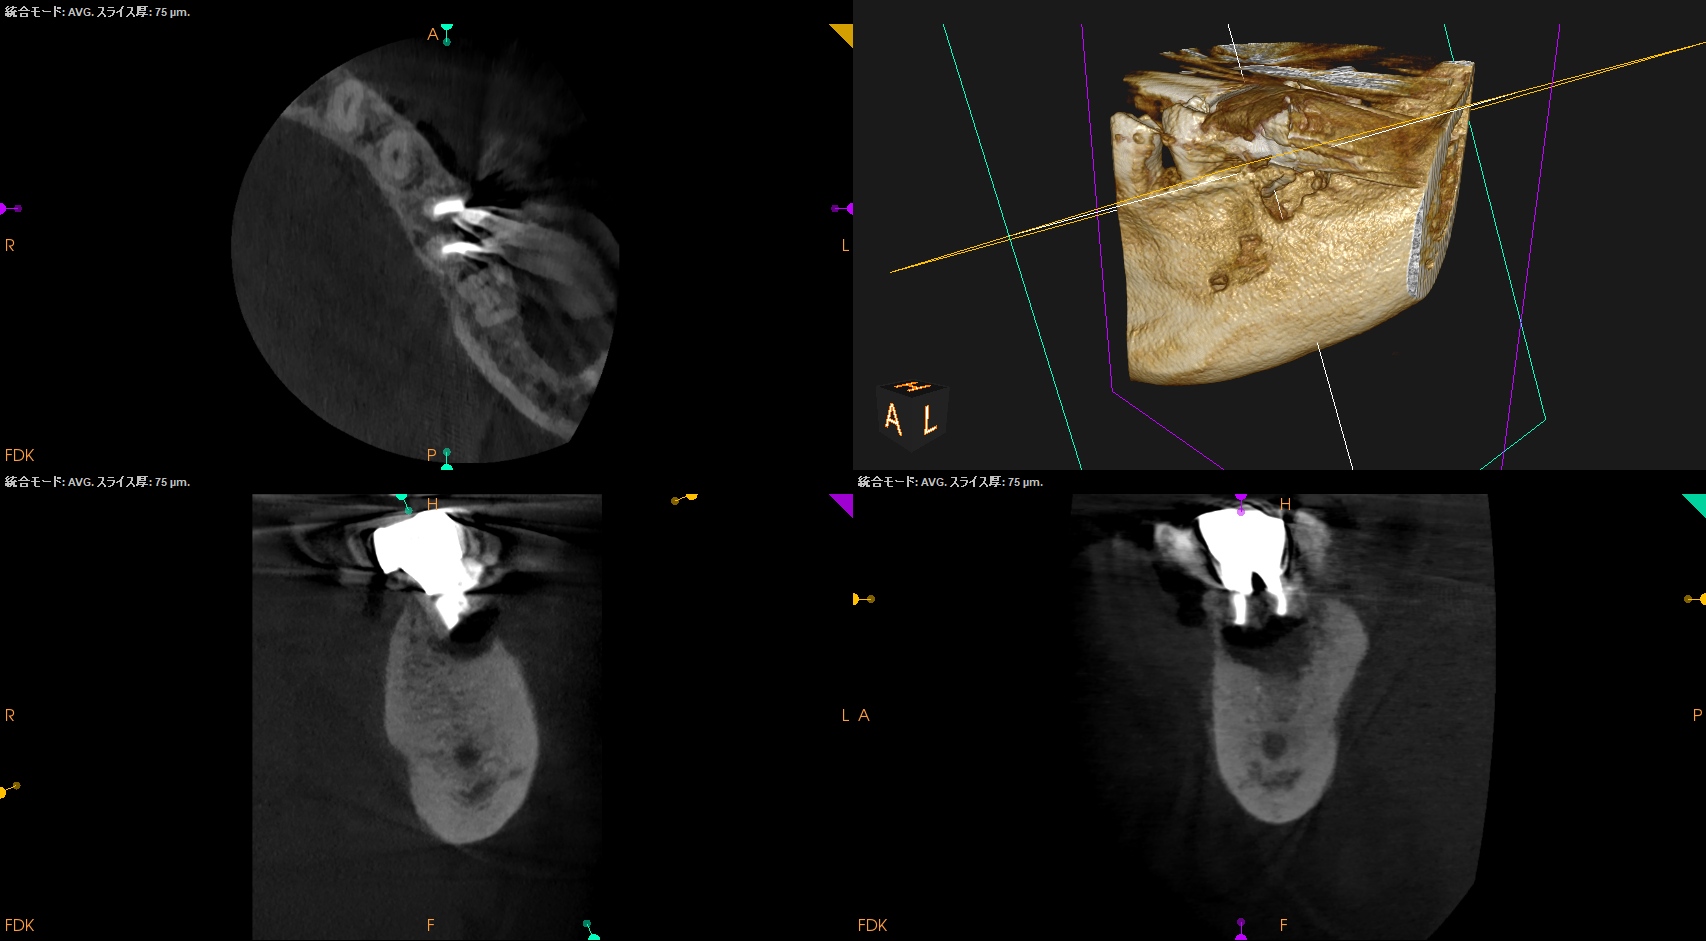

CBCT(2024.9.12)

MB

ML

D

治療はApicoectomyだ。

しかもM,Dともにである。